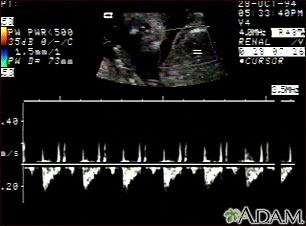

This is a normal fetal ultrasound showing one pattern of the fetal heartbeat. Some ultrasound machines have the ability to focus on different areas of the heart and evaluate the heartbeat. This is useful in the early diagnosis of congenital heart abnormalities.